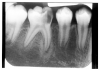

Figure 1 is a molar bitewing radiographic image that discloses a defective abutment restoration on tooth #4. The restoration ends short leaving open margins.

Figure 1 - Defective Restoration; Abutment Tooth #4

Figure 1